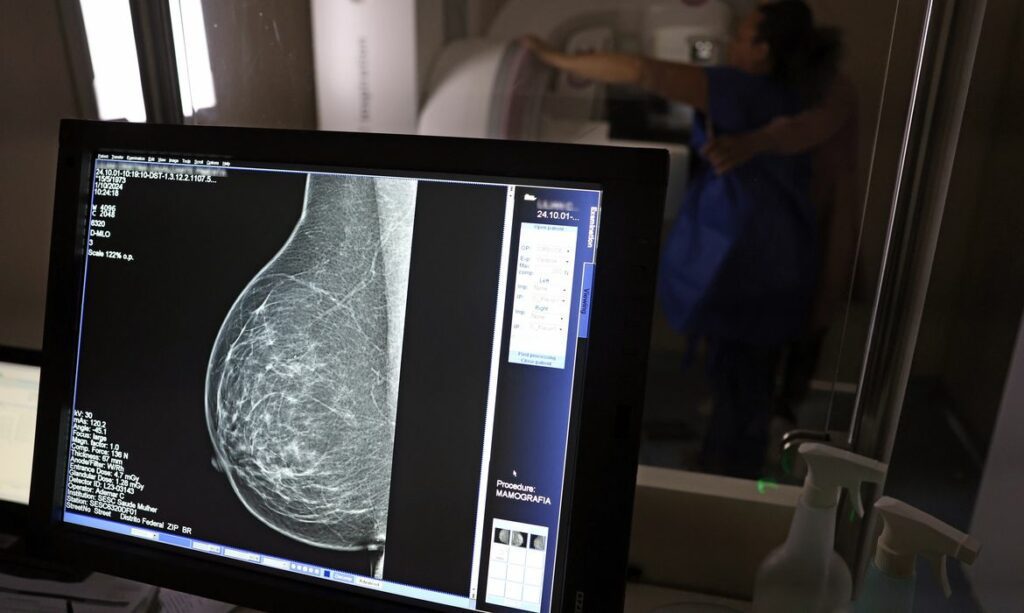

O Ministério da Saúde implementou uma significativa ampliação no acesso à mamografia via Sistema Único de Saúde (SUS), agora recomendando o exame para mulheres a partir dos 40 anos e estendendo a faixa etária para rastreamento ativo até os 74 anos. Essa iniciativa visa fortalecer o diagnóstico precoce do câncer de mama, uma vez que a detecção em fases iniciais aumenta consideravelmente as chances de cura. Anteriormente, a diretriz indicava o início do rastreamento a partir dos 50 anos, o que dificultava o acesso de mulheres mais jovens que não apresentavam sintomas específicos ou histórico familiar.

A nova recomendação estabelece que mulheres entre 40 e 49 anos podem realizar o exame sob demanda, mediante decisão conjunta com um profissional de saúde, mesmo sem manifestar sinais ou sintomas da doença. Esta faixa etária, segundo dados da pasta, concentra cerca de 23% dos casos de câncer de mama. Assim sendo, a mudança busca derrubar barreiras, já que, em anos anteriores, pacientes nessa idade enfrentavam obstáculos na rede pública sem critérios muito específicos.

Nesse sentido, o Ministério da Saúde informou que as mamografias realizadas pelo SUS em pacientes com menos de 50 anos já representam 30% do total. Este número, por sua vez, corresponde a mais de 1 milhão de exames apenas no ano de 2024, evidenciando a demanda e a importância da nova diretriz. Esta ampliação faz parte de um conjunto de ações estratégicas anunciadas recentemente, todas voltadas para aprimorar o diagnóstico e a assistência às mulheres brasileiras.

Adicionalmente, o Ministério da Saúde também expandiu a faixa etária para o rastreamento ativo, que consiste na solicitação preventiva de mamografias a cada dois anos. A idade limite, que antes era de 69 anos, foi estendida para 74 anos. Essa decisão se baseia em dados que revelam a concentração de quase 60% dos casos de câncer de mama entre mulheres de 50 e 74 anos, tornando o rastreamento nesse período crucial para a saúde pública.

A pasta reforçou que a ampliação do acesso à mamografia alinha o Brasil a práticas internacionais de sucesso, como as adotadas na Austrália, e reforça o compromisso governamental em garantir o diagnóstico precoce e o cuidado integral às mulheres. Em conclusão, o câncer de mama é a neoplasia mais comum e a principal causa de morte por câncer entre o público feminino, registrando aproximadamente 37 mil novos casos anualmente no país. Por exemplo, em 2024, o SUS realizou cerca de 4 milhões de mamografias de rastreamento e mais de 376,7 mil exames diagnósticos, números que se espera otimizar com as novas medidas.